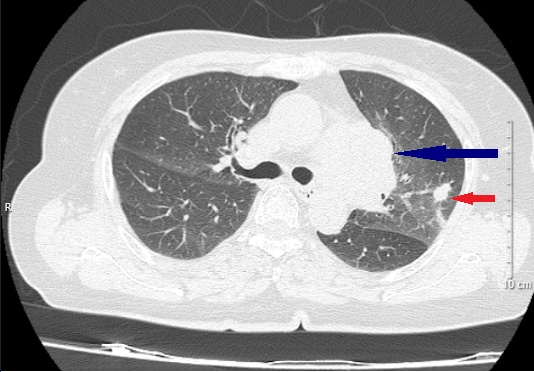

• Chụp cắt lớp vi tính lồng ngực: Trung thất giữa cạnh trái khí quản, rốn phổi trái có khối u với  kích thước 35 x 36 mm, bờ thùy múi, ngấm thuốc không đồng nhất, ôm quanh mạch máu lân cận. Nốt đặc thùy trên phổi trái có đường kính khoảng 10 mm, bờ đều, ranh giới rõ. Không có hạch trung thất.

Hình 1: Hình ảnh cắt lớp vi tính lồng ngực lúc mới chẩn đoán (mũi tên xanh: khối ở trung thất giữa; mũi tên đỏ: nốt đặc ở phổi cùng bên).